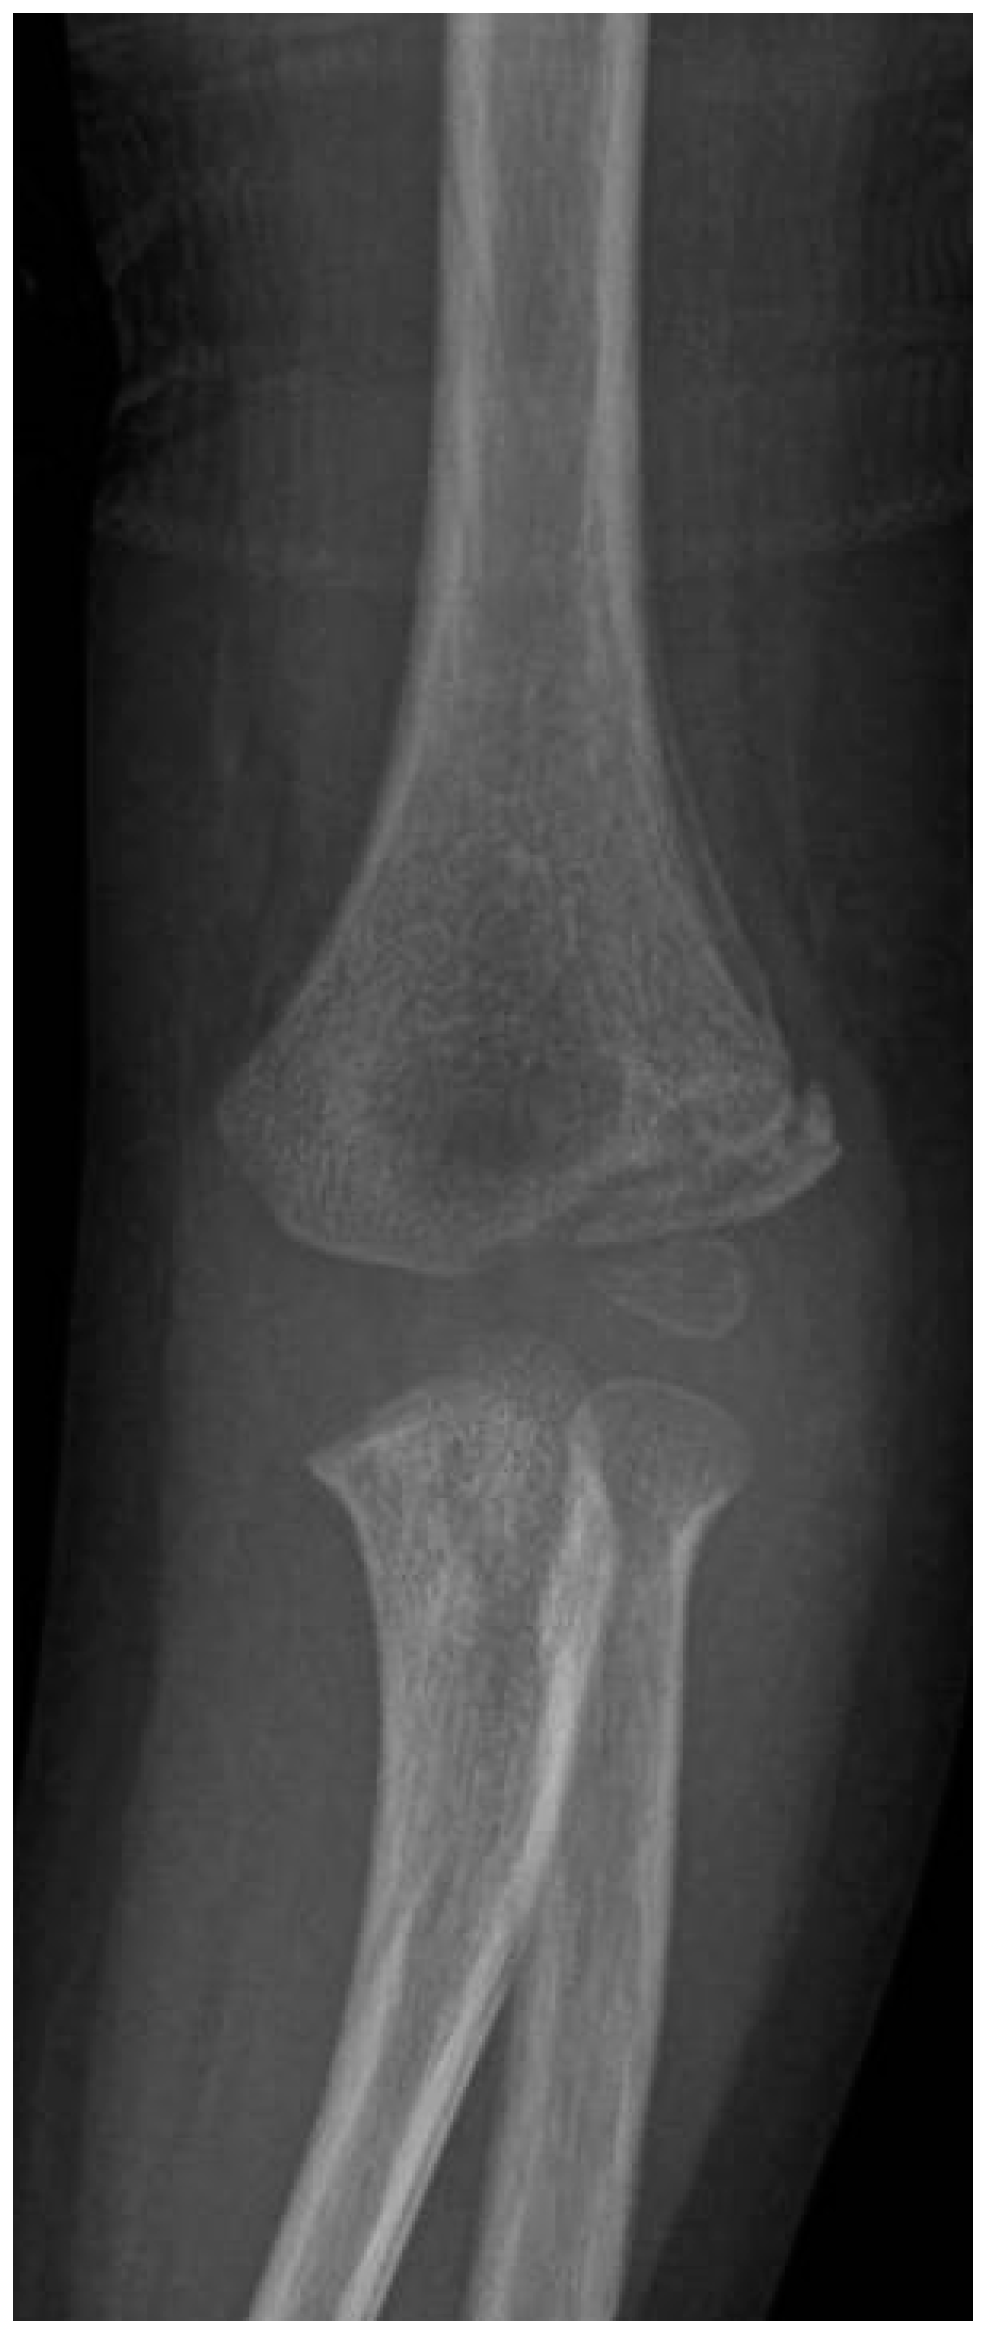

Lateral Humeral Condyle Fracture in Childhood: Results of a New Surgical Technique

1. Introduction